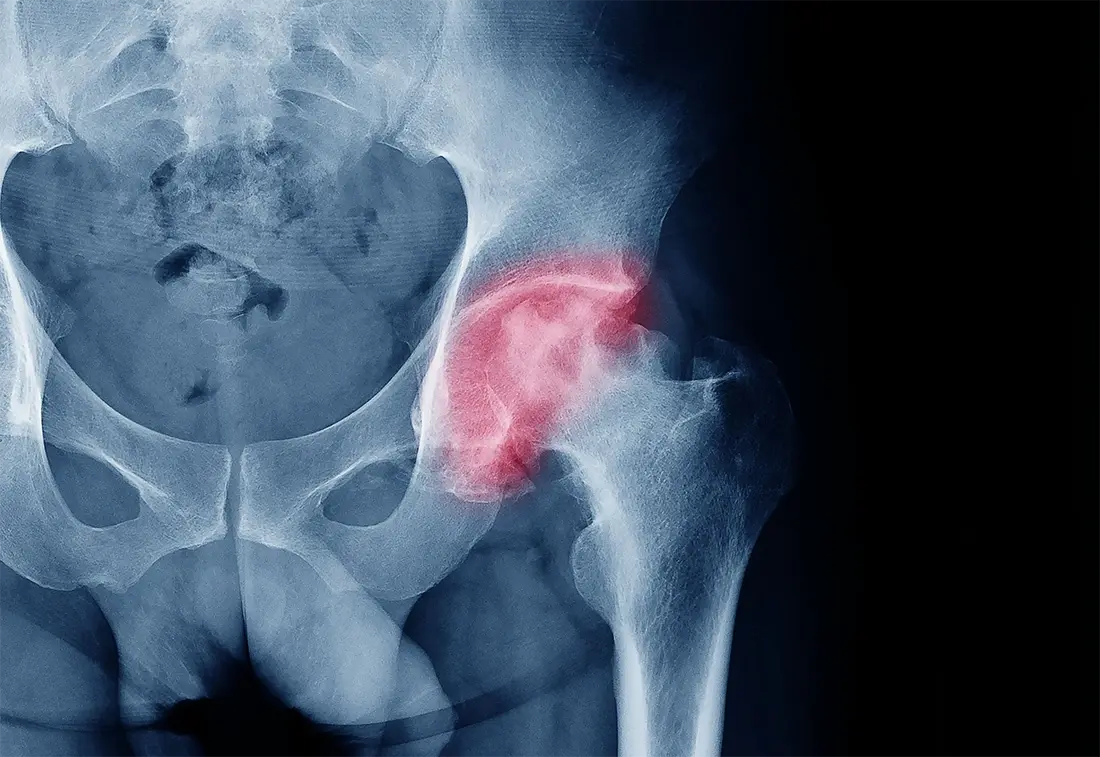

Hip Labral Tear

Hip labral tear is a condition where the cartilage ring surrounding the hip joint tears. This creates pain and stiffness around your hip and also may feel a clicking sensation at the joint. The cause of it can be due to overuse or a dislocation of the joint. Athletes, such as football players, are at a higher risk of sustaining that condition. Compared to muscle strain, this condition is more serious as, apart from the limited mobility, it can lead to osteoarthritis in the future. Treatment options include painkillers, corticosteroid injections, physical therapy or surgery to repair the cartilage.